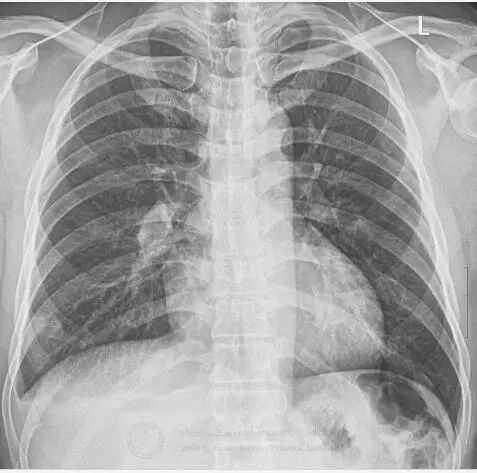

图1 右肺下叶区域胸膜肿块样阴影,以及肋膈角钝化。